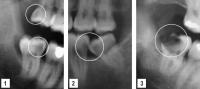

Decay Example

- Extensive decay affecting upper and lower impacted wisdom tooth

- Impaction of lower wisdom tooth leading to development of decay in the lower second molar

- Extensive decay affecting impacted lower wisdom tooth

Impacted Wisdom Teeth

Impacted wisdom teeth can also adversely affect the attachment of adjacent teeth or be associated with cystic lesions.

- Horizontally impacted wisdom tooth adversely affecting attachment of second molar

- Extensive cystic development around impacted lower wisdom tooth